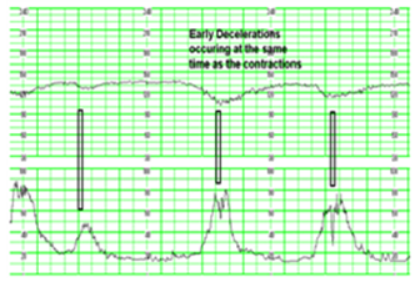

⓵ 조기 감퇴(조기하강) – early deceleration

FHR은 자궁 수축과 함께 시작되며 자궁 수축이 끝나면 기본선으로 회복

원인 : 아두압박(태아의 머리가 압박되어 미주신경자극이 커지고 심박수는 떨어진다)

간호 중재: 정상적인 반응이므로 관찰 및 기록(초기 활동기/FHR 하강은 최저 심박수 수준으로 감소/단기간 일정한 형태, 반복적으로 발생)